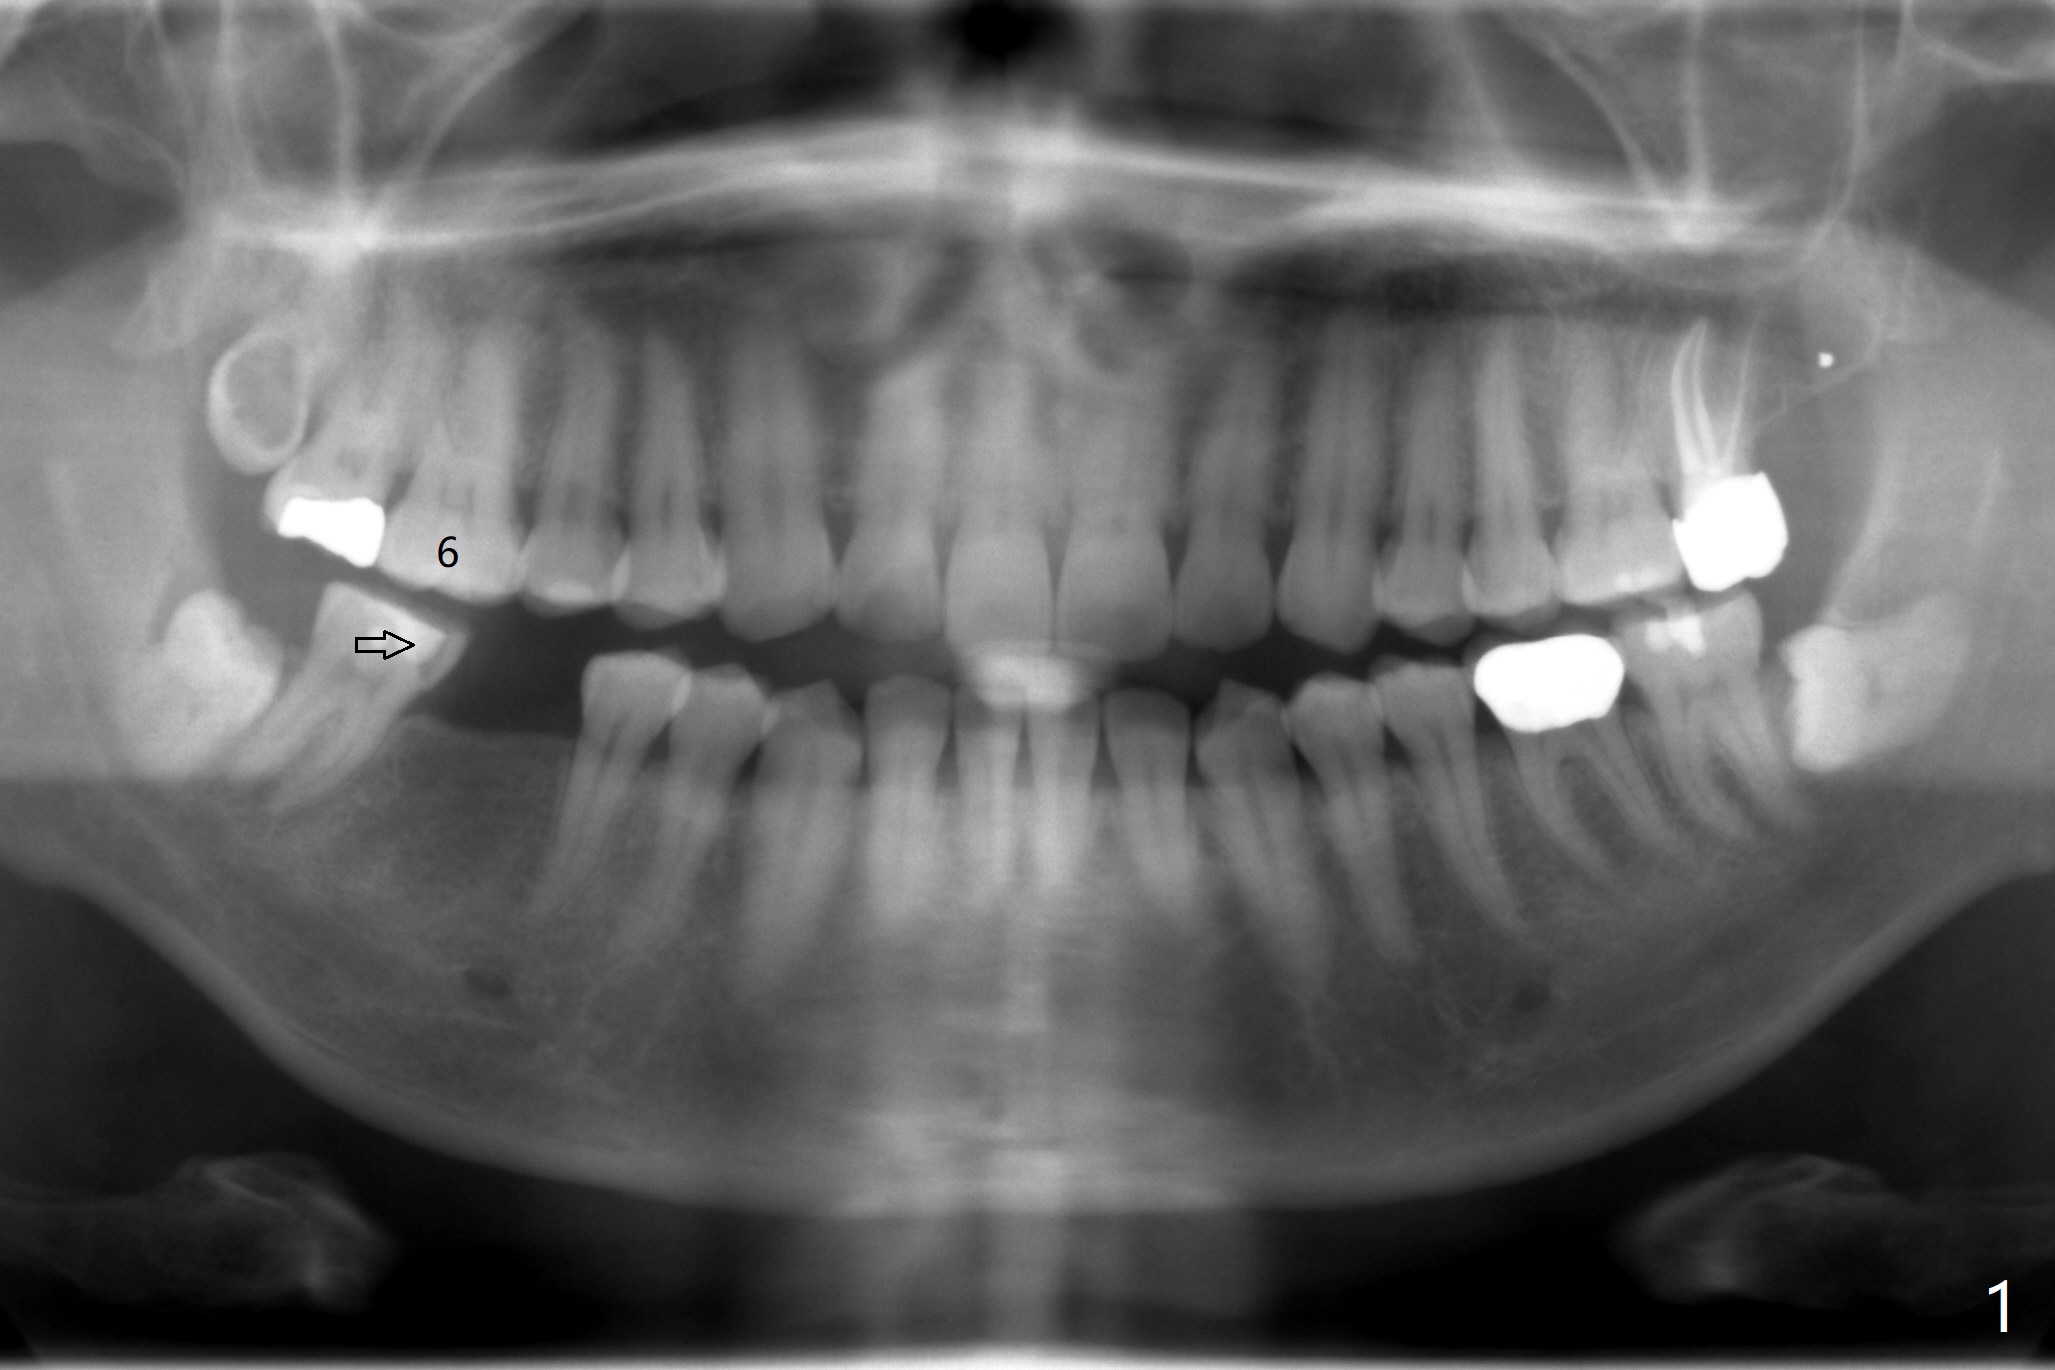

54岁男缺失右下6大约20-30年,但是右上6却没有过度萌出,因为右下7好像近中移位(图一:箭头)。3年前在没有CT检查下,根尖片设计表示植体直径可以4.5毫米(图二)。尽管现在CT检查表明骨头颊舌侧宽度允许5毫米植体(图三),4.5毫米植体(缺牙区近远中间隙小)可以让植体颊侧,舌侧骨板接近2毫米,加上导板应用,以及足够角化龈(临床检查显示),延长植体寿命是比较现实的事情。